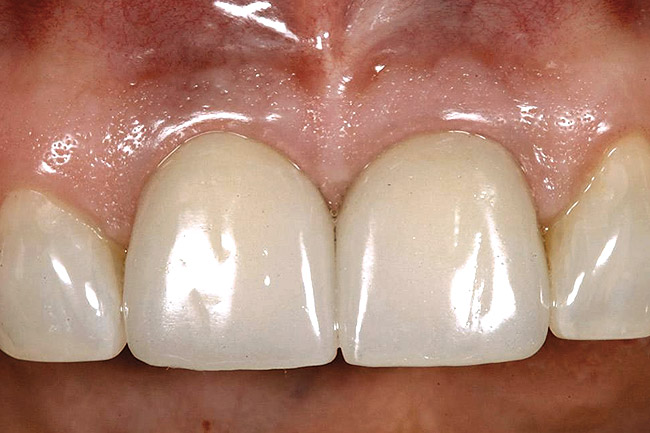

Figure 25  A patient presented with a significant ridge defect, but with surgeon-placed adjacent implants in the lateral and cuspid positions.

Figure 25

Figure 26  A pediculated connective-tissue graft was used to augment the soft-tissue height.

Figure 26

Figure 27  The lateral incisor implant was put to sleep and the cuspid implant uncovered.

Figure 27

Figure 28  The final restoration exhibits a cantilevered incisor off of a canine implant.

Figure 28